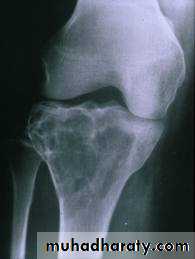

show a radiolucent area situated eccentrically at the end of a long bone and bounded by the sub- chondral bone plate.

The endosteal margin may be quite obvious, but in aggressive lesions it is ill-defined.

X-rays42

The Centre sometimes has a soap-bubble appearance.

The cortex is thin and sometimes ballooned. aggressive lesions extend into the soft tissue.43

The appearance of a ‘cystic’ lesion in mature bone, extending right up to the subchondral plate, is so characteristic